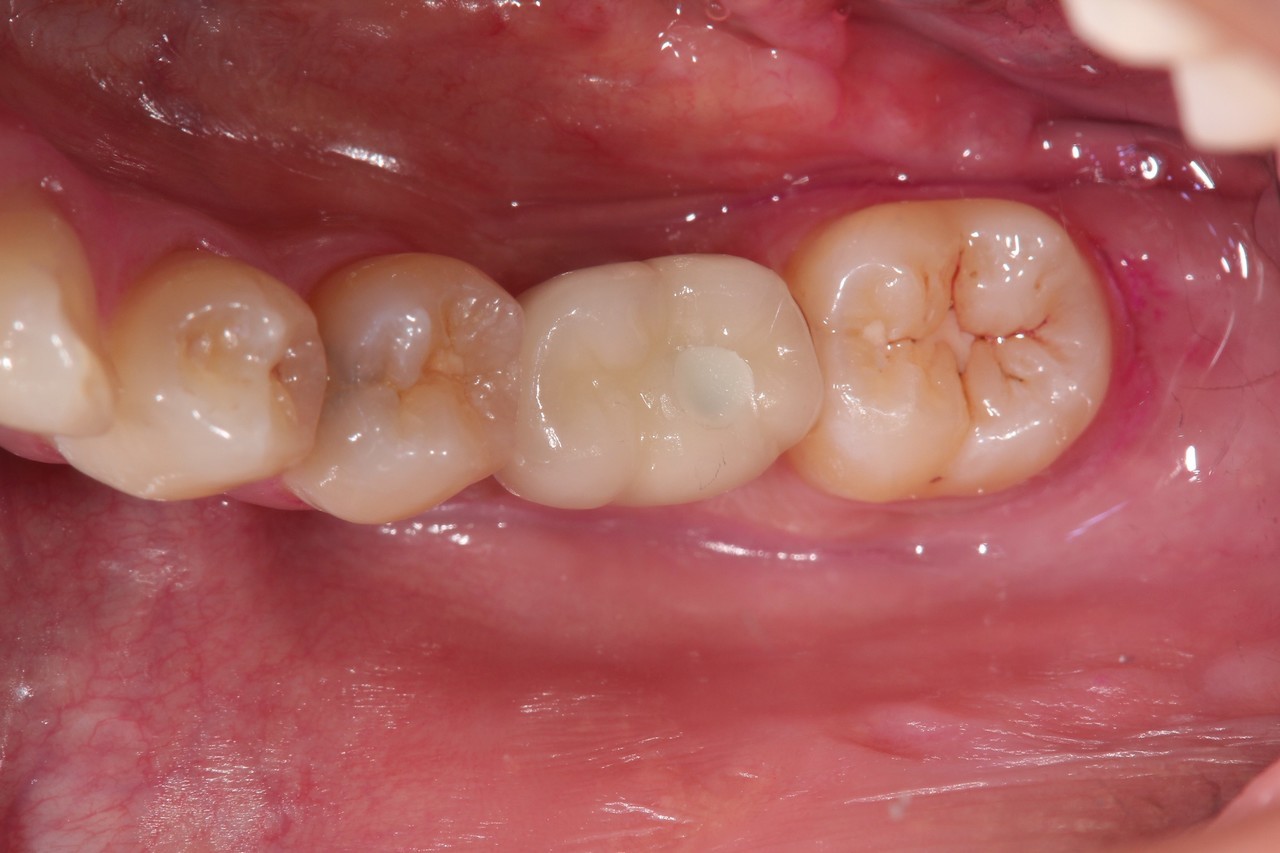

奥歯インプラント(スクリュー固定)

(伊東市 女性)

治療の流れ

むし歯で歯を失ってしまいました。

インプラントを埋入し、最終的な被せ物を装着しました。(ネジ穴をふさぐ前)

ネジ穴をふさぐとこの様な状態になります。